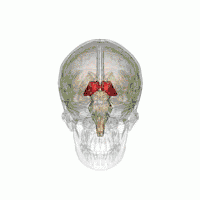

![]() Таламус человека на МРТ-снимке, отмечен стрелкой | |

Тала́мус, иногда — зри́тельные бугры (лат. thalamus; от др.-греч. θάλαμος «комната, камера, отсек») — отдел головного мозга, представляющий собой большую массу серого вещества, расположенную в верхней части таламической области промежуточного мозга хордовых животных, в том числе и человека. Впервые описан древнеримским врачом и анатомом Галеном. Таламус — это парная структура, состоящая из двух половинок, симметричных относительно межполушарной плоскости. Таламус находится глубже структур большого мозга, в частности коры или плаща. Под таламусом расположены структуры среднего мозга. Срединная (медиальная) поверхность обеих половинок таламуса одновременно является верхней боковой стенкой третьего желудочка головного мозга[1][2][3].

Таламус расположен вблизи центра мозга и входит в число структур таламической области промежуточного мозга. Он залегает под структурами большого мозга, но возвышается над структурами среднего мозга. Восходящие аксоны, исходящие из нейронов ядер таламуса, формируют пучки миелинизированных нервных волокон. Эти пучки нервных волокон обильно проецируются на различные области коры больших полушарий головного мозга во всех направлениях. Медиальная поверхность обеих половинок таламуса одновременно является верхней частью боковой стенки третьего желудочка головного мозга. Она соединена с соответствующей медиальной поверхностью противоположной половинки таламуса плоской полосой белого вещества. Эта полоса представляет собой пучок миелинизированных нервных волокон и называется межталамическим сращением, или промежуточной массой третьего желудочка, или срединной комиссурой (срединной спайкой) таламуса.